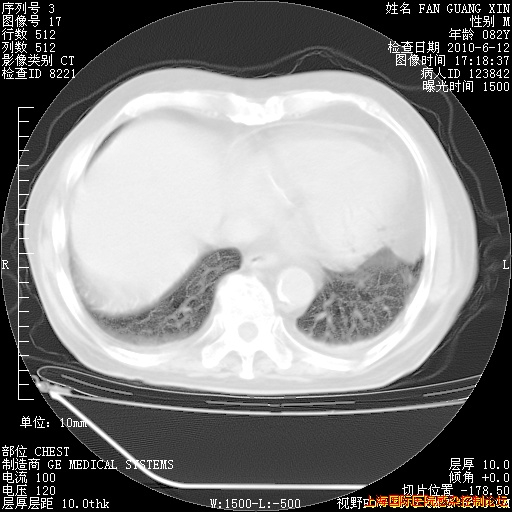

补发6月12日肺部CT肺窗

6月12日肺窗